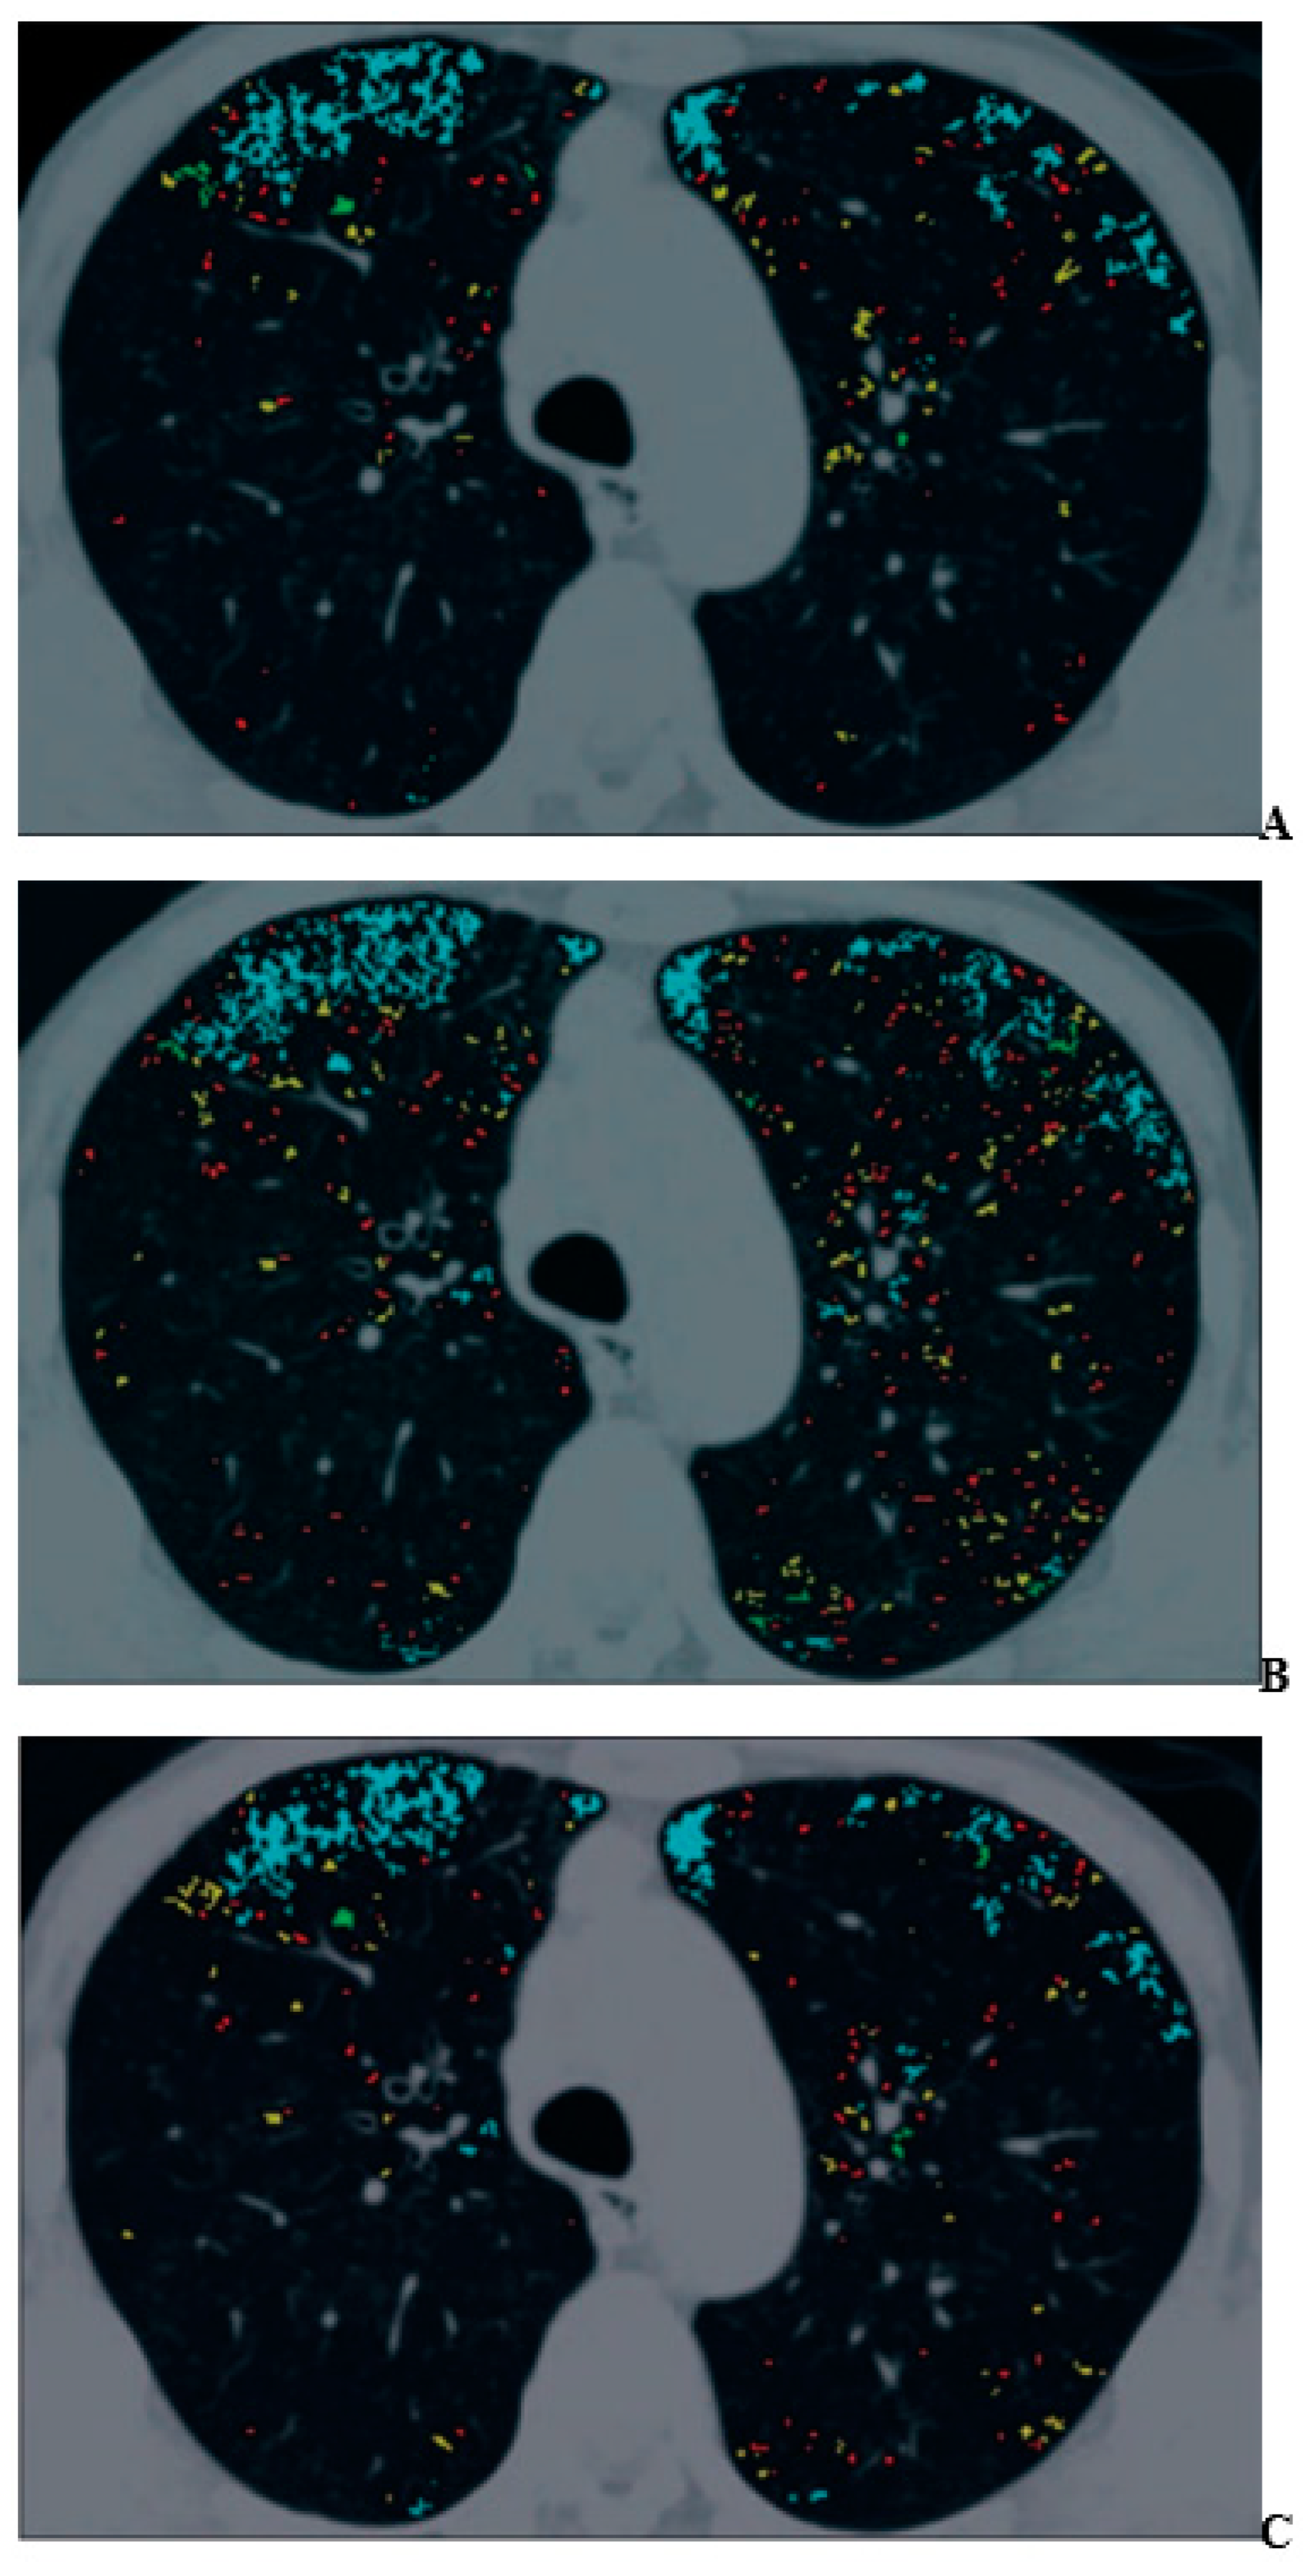

- Ohno, Y.; Aoyagi, K.; Takenaka, D.; Yoshikawa, T.; Ikezaki, A.; Fujisawa, Y.; Murayama, K.; Hattori, H.; Toyama, H. Machine learning for lung CT texture analysis: Improvement of inter-observer agreement for radiological finding classification in patients with pulmonary diseases. Eur. J. Radiol. 2021, 134, 109410. [Google Scholar] [CrossRef] [PubMed]

- Ohno, Y.; Aoyagi, K.; Arakita, K.; Doi, Y.; Kondo, M.; Banno, S.; Kasahara, K.; Ogawa, T.; Kato, H.; Hase, R.; et al. Newly developed artificial intelligence algorithm for COVID-19 pneumonia: Utility of quantitative CT texture analysis for prediction of favipiravir treatment effect. Jpn. J. Radiol. 2022, 40, 800–813. [Google Scholar] [CrossRef] [PubMed]

- Ohno, Y.; Aoyagi, K.; Takenaka, D.; Yoshikawa, T.; Fujisawa, Y.; Sugihara, N.; Hamabuchi, N.; Hanamatsu, S.; Obama, Y.; Ueda, T.; et al. Machine learning for lung texture analysis on thin-section CT: Capability for assessments of disease severity and therapeutic effect for connective tissue disease patients in comparison with expert panel evaluations. Acta Radiol. 2022, 63, 1363–1373. [Google Scholar] [CrossRef]